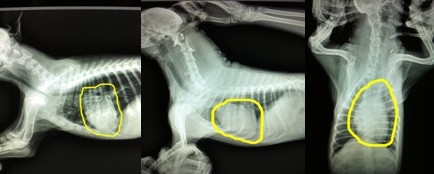

上圖中分享的依然是剛才的兩只犬的三張X光片,但是重點不一樣,通過圖片畫圈的位置可以發(fā)現(xiàn),第一只犬是主要由于氣管狹窄,通氣不足引起的喘氣急促。第二張圖片,圖片中心臟的面積幾乎占了整個胸腔的一半,形狀也有明顯的異常,而氣管并沒有明顯異常影像,另外通過醫(yī)生的聽診和第三張不同體位的X光片的檢查分析,可確診此犬患有心臟病。X光片的確診對于心臟病十分重要,醫(yī)生會通過專業(yè)的測量和計算來判斷心臟病的類型和嚴(yán)重程度。